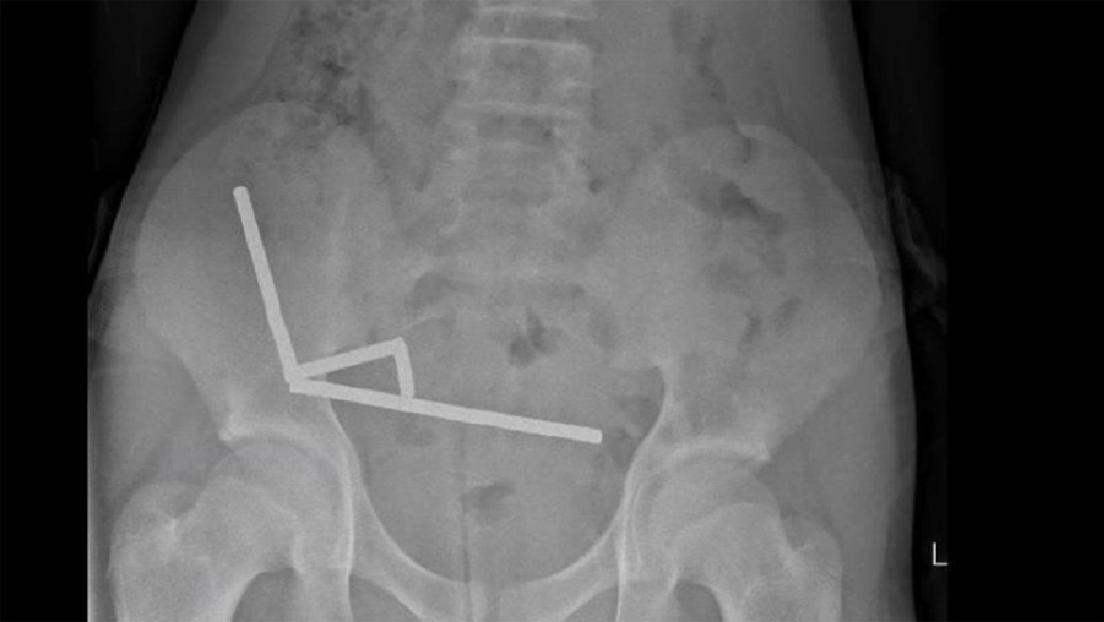

Mediante una radiografía, los médicos visualizaron cuatro cadenas lineales en diferentes partes del intestino del paciente. Una vez dentro, los pequeños objetos metálicos se unieron de forma destructiva.